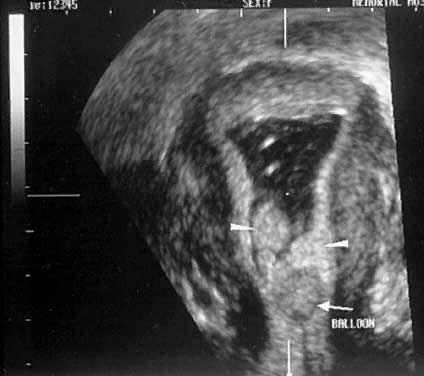

The technique of sonohysterography is relatively simple. The possibility of pregnancy must be excluded. Patients with a history of pelvic inflammatory disease should be treated prophylactically with antibiotics. A single-hinged speculum is helpful but not required. The cervix is cleaned. A 5-French sonohysterogram catheter (Ackrad Laboratories, Cranford, NJ, USA) (Fig. 10) can be inserted into the lower uterine segment or cervical canal in most menopausal patients without a tenaculum or dilators. A 7-French catheter is used for patients with a more dilated cervix to obtain better occlusion with the larger balloon size. The catheter should be flushed before insertion to avoid air bubbles during the procedure. The vaginal probe ultrasound is inserted, and the sonohysterogram is performed, usually requiring less than 10 ml of saline. The cavity should be assessed in multiple transverse and longitudinal cuts. Vagal episodes can occur, particularly in women who have not had children. Premedication in nulliparous patients with nonsteroidal antiinflammatory drugs (NSAIDs) such as ibuprofen or naproxen (Naprosyn) is recommended. The role of three-dimensional imaging is investigational26 (Figs. 11 and 12).

Fig. 10. This sonohysterogram catheter is used in our laboratory.